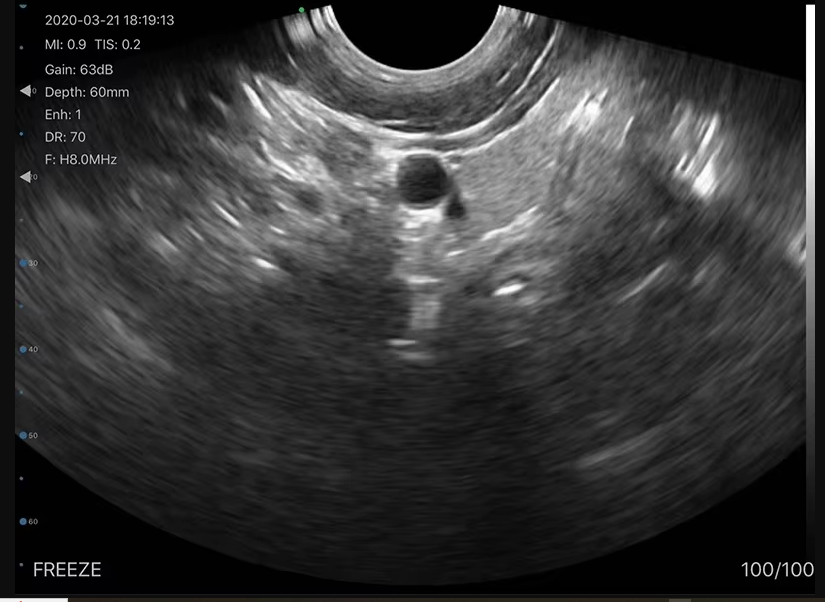

This model features Convex + TVS scanning modes in one device. That means you can easily switch between abdominal scanning and transvaginal imaging without changing probes. This makes it a cost-saving and time-saving ultrasound equipment for clinics and hospitals.

High-Quality Imaging

With advanced digital imaging technology, this wireless ultrasound probe price in Bangladesh offers excellent image clarity, deep penetration, and low noise. It helps doctors make quick and accurate diagnoses, improving patient care.

Gynecology & Obstetrics

Pregnancy Monitoring

Absolutely. The Convex + TVS combination makes it ideal for OBGYN and pregnancy diagnosis.